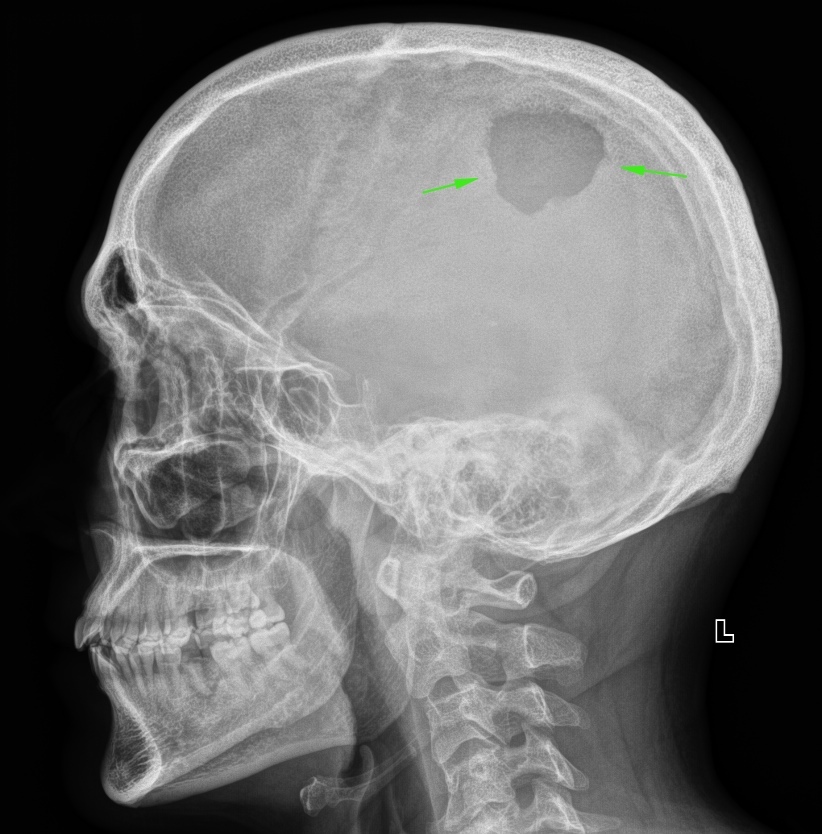

Рентгенография черепа и позвоночника: изображение и диагностика